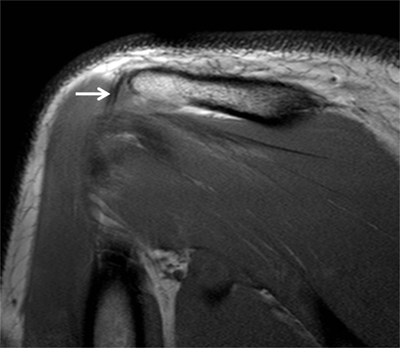

Figure 3

Subchondral cysts of the humeral head and normal bare area. (A) Axial and (B) Coronal oblique fat-suppressed T1-weighted MR arthrographic images show subchondral cysts at the attachment of the infraspinatus tendon (arrow). Coronal oblique section of the same patient discloses a normal bare area in the posterolateral aspect of the humeral head with small fibrocystic changes that communicate with the joint and should not be mistaken for a cartilage defect (arrow, B). Such changes are common and often asymptomatic.